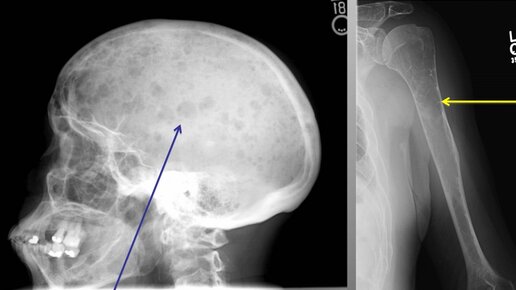

Сегодня вспомнила свою пациентку, девочка, девчушка совсем, приехала к нам- в лежачем состоянии, красоты несусветной, это честно и правда. Смотрю на направление- метастазы в позвоночнике и костях, первичная опухоль не выявлена. Девчушка на удивление, очень даже позитивная, родные- всем бы таких. Какие-то сомнения у нас закрались в душу… Или может нежелание принимать ситуацию, не знаю, но было какое-то чувство, что-то здесь не так… Ей проводили множество исследований, в т.ч. рентген снимков, она устала от боли, от обследования, от невозможности ходить и быть самостоятельной...